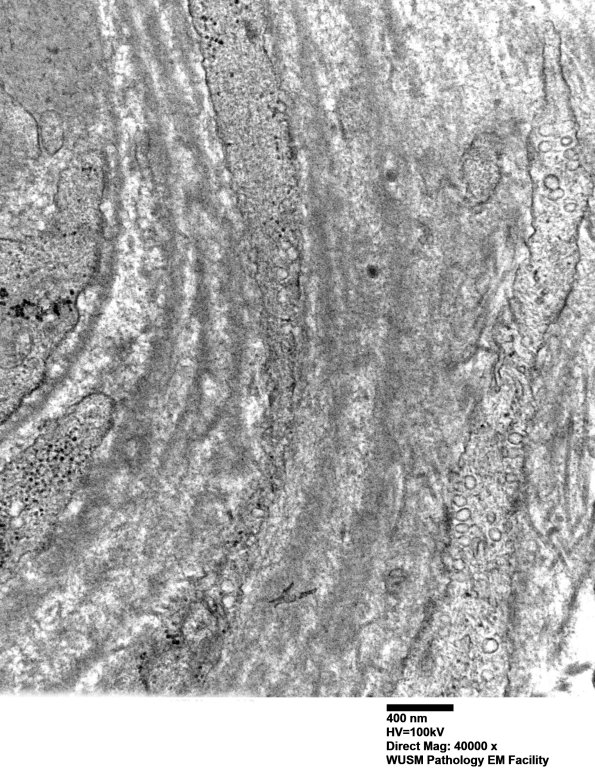

Washington University Experience | VASCULAR | Hypoxia-Ischemia, fetal-neonatal | White Matter | 14B3C (Case 14) EM019 - Copy

14B3C (Case 14) EM019 - Copy